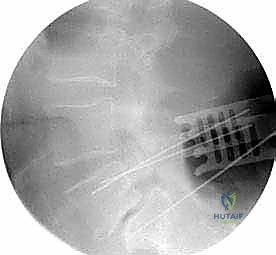

عملية دمج الفقرات (Spinal Fusion) هي إجراء جراحي يهدف إلى ربط فقرتين أو أكثر بشكل دائم، مما يزيل الحركة غير الطبيعية والمؤلمة بينهما، ويعيد الاستقرار الميكانيكي إلى العمود الفقري. في حالتنا هذه، يتم التركيز بشكل خاص على المنطقة الصدرية القطنية (Thoracolumbar Junction)، وهي المنطقة الانتقالية الحرجة التي تربط الجزء العلوي من الظهر (القفص الصدري الصلب) بالجزء السفلي (المنطقة القطنية المتحركة). يتم التثبيت باستخدام أدوات طبية معدنية متطورة (Instrumentation) مثل المسامير السويقية (Pedicle Screws) والقضبان المصنوعة من التيتانيوم.

- تبني أحدث التقنيات التكنولوجية: يستخدم د. هطيف تقنيات الجراحة الميكروسكوبية الدقيقة (Microsurgery)، ومناظير المفاصل بدقة 4K، وأنظمة الملاحة الجراحية لضمان وضع المسامير بدقة متناهية (Sub-millimeter accuracy) وتجنب أي إصابة للأعصاب.